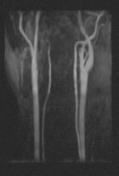

Fig・5  SORS-STCパルスを用いた頸部MRA

TR30 TE6.8 FA20 ISCE1:3 2スラブ SORS-STCパルス300deg